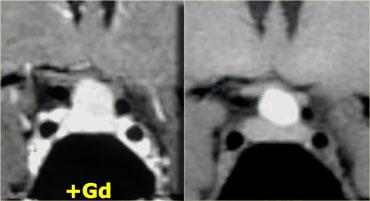

Hình ảnh chuỗi xung T1W và T2W mặt phẳng coronal, cùng với hình ảnh chuỗi xung T1W trước và sau tiêm gadolinium.

Ở bệnh nhân này, tổn thương trong tuyến yên chỉ có thể phát hiện được sau khi tiêm thuốc tương phản từ đường tĩnh mạch.

Chẩn đoán phân biệt: u tuyến yên vi thể hoặc nang khe Rathke.